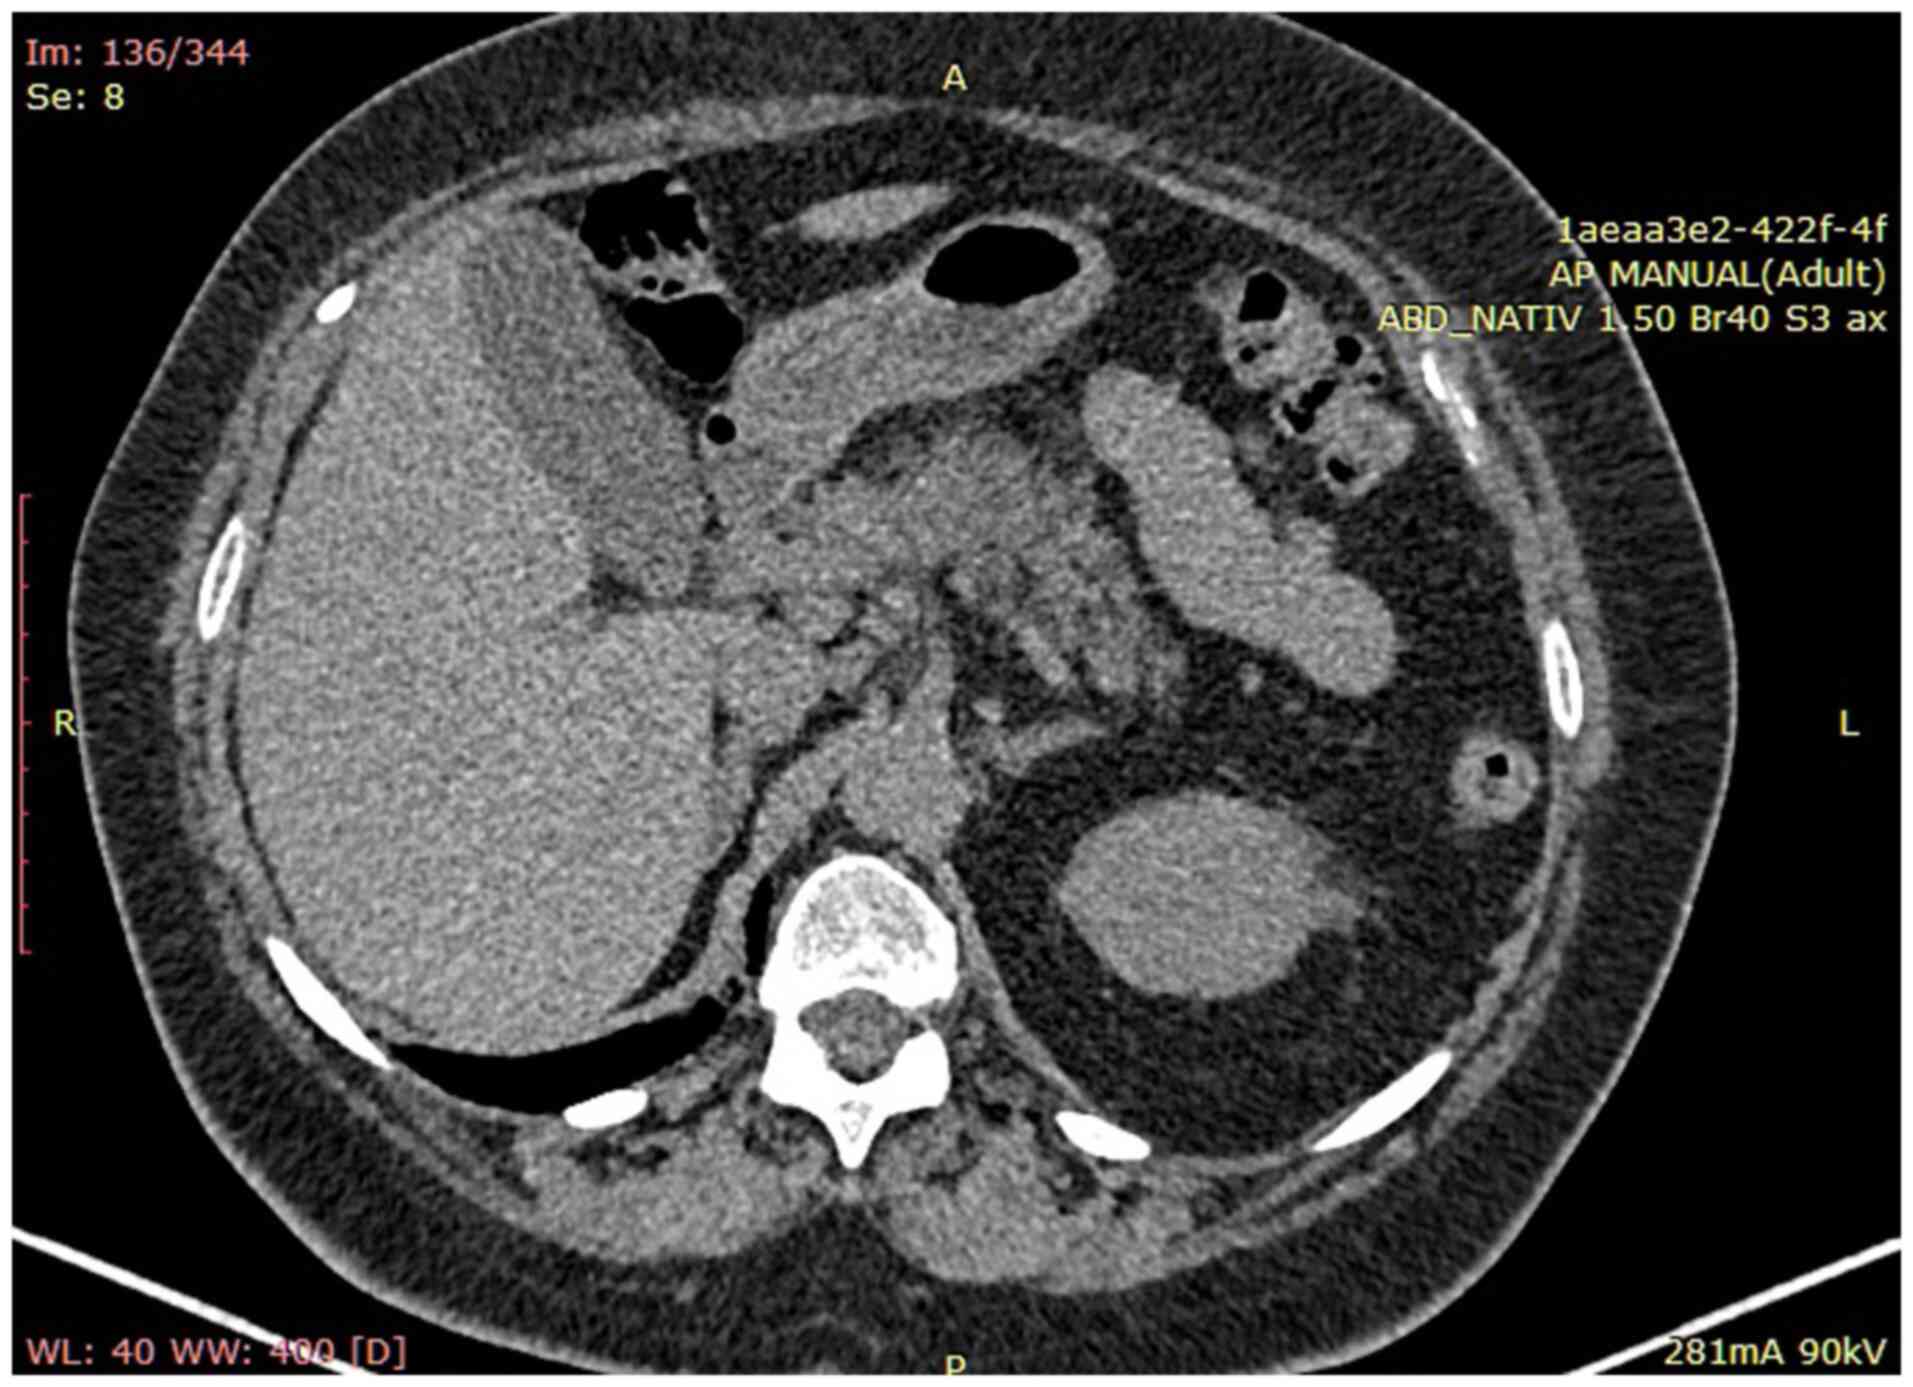

Abdominal computed tomography (CT) scan confirmed liver enlargement without pathological masses, normal diameter (12 mm) of the portal vein and a notable accumulation of ascitic fluid. Additionally, CT scan revealed multiple mesenteric lymphadenopathy, measuring up to 1.3 cm, and increased renal echogenicity. No pathological alterations were observed in the spleen, prostate, or pancreas (Fig. 1).

Figure 1

Abdominal CT scan confirmed liver enlargement without pathological masses, a normal portal vein diameter, multiple mesenteric lymph nodes measuring up to 1.3 cm and increased renal echogenicity.